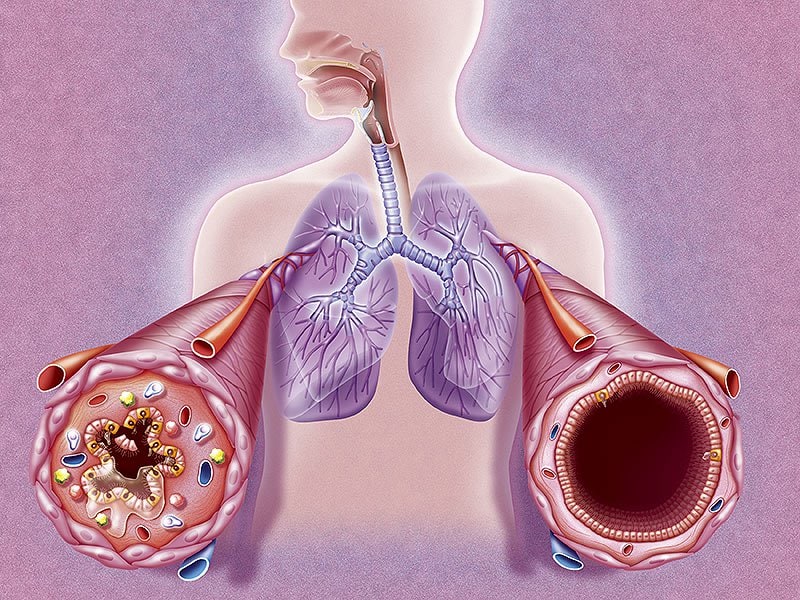

Фотографии и информация о бронхоскопии при туберкулезе